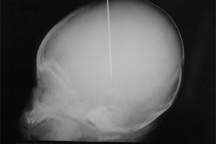

Tôi thực sự phẫn nộ trước con người này. Việc hành hung 1 đứa trẻ mới 40 ngày tuổi hoàn toàn không có khả năng tự vệ đã là không thể chấp nhận được chứ đừng nói đến đóng kim khâu ngập vào thóp cháu bé như thế. Con người này quá dã man, hành vi đó thật không thể nương nhẹ, khởi tố về tội giết người là hoàn toàn xứng đáng, hãy để chị ta nhận hình phạt cao nhất.